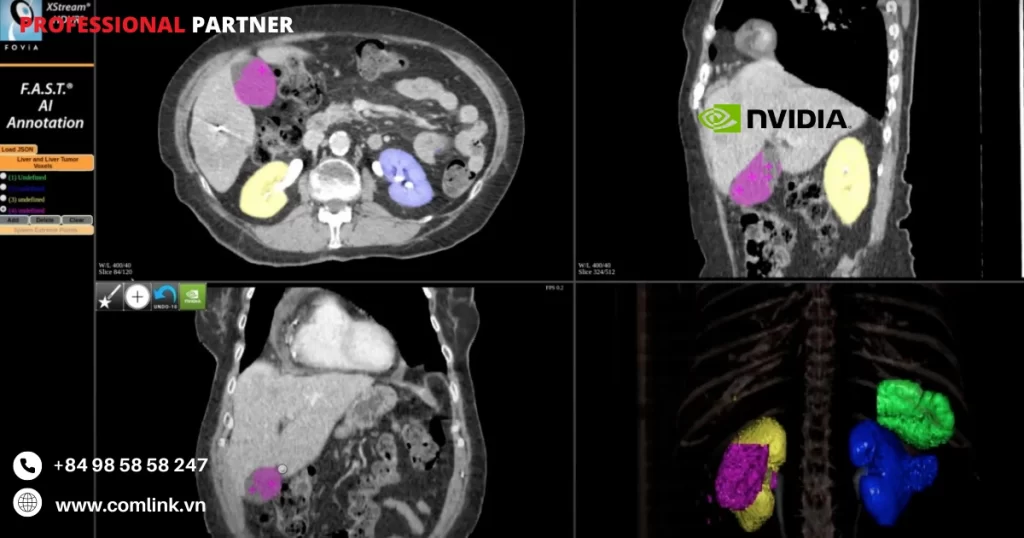

Một trong những ứng dụng quan trọng của giải pháp là tăng cường khả năng chẩn đoán trong hình ảnh y khoa.

Các mô hình trí tuệ nhân tạo trong Nvidia Monai có khả năng phân loại và nhận dạng các biểu hiện bất thường trong hình ảnh y khoa.

Điều nay giúp các chuyên gia y tế chẩn đoán và điều trị bệnh nhanh chóng và chính xác.

Giải pháp cho phép xây dựng các mô hình trí tuệ nhân tạo để phân loại và nhận dạng các bệnh trong hình ảnh y khoa.

Các mô hình này có khả năng tự động phân loại các biểu hiện bất thường, giúp chẩn đoán và điều trị bệnh nhanh chóng và chính xác.

Ví dụ: giải pháp có thể được sử dụng để phát hiện ung thư từ hình ảnh X-quang hoặc MRI.

Xử lý ảnh y khoa

Giải pháp cung cấp các công cụ và thuật toán tiên tiến để xử lý ảnh y khoa.

Các công cụ này có thể được sử dụng để làm sạch, chuẩn hóa và biến đổi các hình ảnh y khoa trước khi áp dụng các mô hình trí tuệ nhân tạo.

Ví dụ: Giải pháp có thể được sử dụng để loại bỏ nhiễu hoặc cải thiện chất lượng hình ảnh y khoa.

Tạo ra hình ảnh tổng quan cao cấp

Nvidia Monai có khả năng xây dựng các mô hình trí tuệ nhân tạo để tạo ra hình ảnh tổng quan cao cấp từ các loại dữ liệu y khoa khác nhau.

Ví dụ: Giải pháp có thể được sử dụng để tạo ra hình ảnh toàn cầu của não từ nhiều loại hình ảnh MRI khác nhau, giúp các chuyên gia y tế có cái nhìn tổng quan về bệnh nhân.